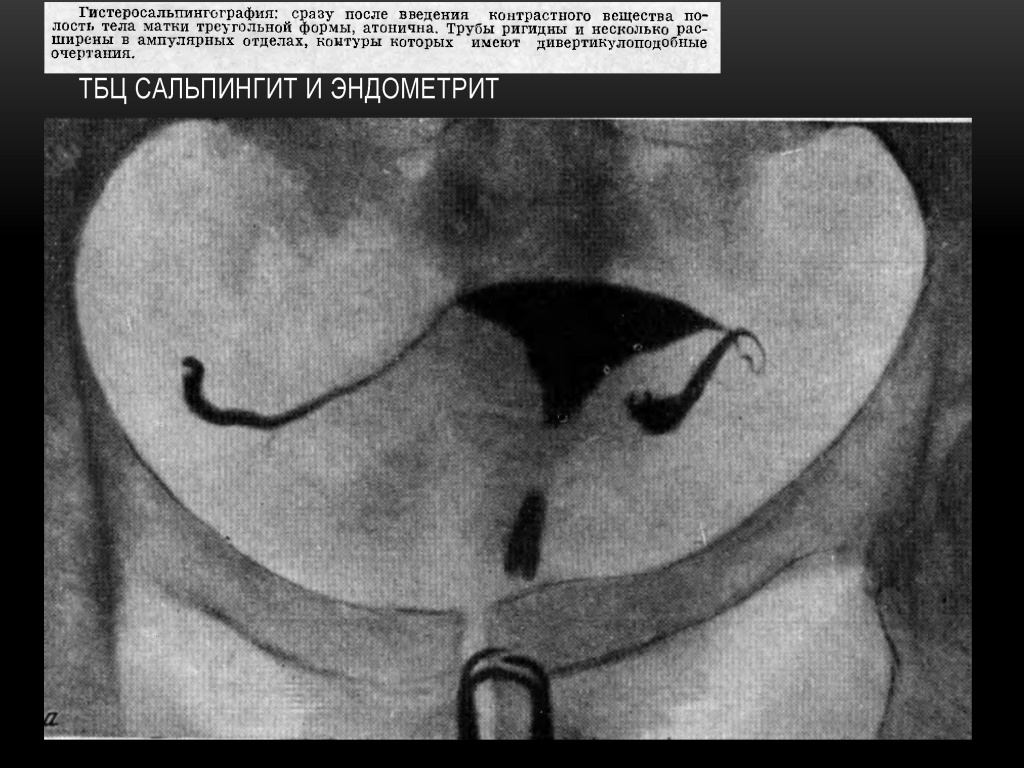

Туберкулез половых органов: 3 варианта по Мадсен

• Неровные контуры труб, состоящие как бы из отдельных сегментов

• Гладкие, ригидные, сплошные контуры труб ,напоминающие по форме трубку для курения («толщиной с карандаш»)

• Фистулоподобные расширения труб

Вероятные признаки туберкулеза: истмическая часть трубы сужена, множественные складки в ампулярном отделе, напоминающие фистулезные ходы; перистальтика в трубах отсутствует.

Весьма вероятные признаки: небольшая деформированная полость тела матки (1/5 или % длины канала шейки матки), интравазация матки, перистальтика в трубах отсутствует - ригидны; на концах труб расширения - как «ватные затычки».

Надежные признаки: кальцификация л/узлов, яичников и труб

ТБЦ поражает ампулярный и истмический отделы труб в виде облитерации просвета ампулярного отдела, истмические отделы ригидные, нередко расширены и заканчиваются бульбообразными утолщениями на конце. Рентгенологически - «трубка для курения».

При туберкулёзном эндометрите в далеко зашедших случаях возникает деформация полости матки, частичная или полная её облитерация. На рентгенограмме - резко деформированная, небольших размеров полость матки.

Признаки туберкулеза внутренних женских половых органов.

1. Трубы с гладкими или неровными контурами, закрытые в начале ампулярного или в истмическом отделе, с небольшим расширением в конце в виде луковицы — bulbus, либо булавоподобные или .дубиноподобные.

2. Трубы ригидные (отсутствие перистальтики), как бы окостеневшие, с гладкими контурами, с широким или узким просветом, закрытые в истмическом или ампулярном отделе.

3. Трубы, контуры которых похожи на четки, бусы или сегменты, т. е. с множественными стриктурами в ампулярном или истмическом отделе.

4. Трубы с кистоподобными или фистул оподобньми полостями.

5. Трубы с умеренными гидросальпинксами и с дивертикулоподобными контурами.

6. Кальцификация труб, яичников, лимфатических узлов также является надежным признаком туберкулеза внутренних половых органов.

7. Деформация полости тела матки в сочетании с описанной выше рентгенологической картиной труб дает возможность правильно поставить диагноз туберкулеза матки и труб. Следует подчеркнуть, что при нормальной конфигурации полости матки диагноз туберкулеза внутренних поло¬вых органов ставится на основании рентгенологической картины труб